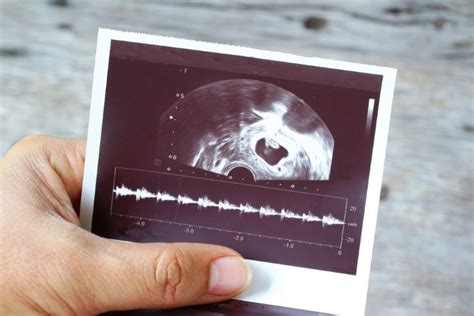

Unul din scopurile principale ale ecografiei este diagnosticul și confirmarea prezenței unei sarcini în cavitatea uterină. Astfel, sacul gestațional poate fi observat și măsurat la o vârstă a sarcinii de 4-5 săptămâni, iar embrionul poate fi vizualizat la 5-6 săptămâni; examinarea transvaginală permite vizualizarea mai timpurie, cu aproximativ o săptămână mai devreme comparativ cu ecografia transabdominală.

Prima întrebare a viitorilor părinți după ce află că urmează să aibă un copil este „când se vede embrionul la ecograf?”. Răspunsul variază, însă embrionul devine vizibil începând cu săptămâna 5-6. Aceasta este perioada când se poate observa un punct mic cu activitate cardiacă.

Embrionul se vede la ecografie la aproximativ 6-7 săptămâni de gestație, împreună cu bătăile inimii fetale.

Aceasta este una dintre cele mai emoționante etape pentru părinți, deoarece este momentul în care bătăile inimii bebelușului pot fi auzite pentru prima dată.

Atunci când embrionul ajunge la circa 5 mm (6 săptămâni și 3 - 4 zile) devine vizibilă activitatea cardiacă sub forma unui punct ce se mișcă/pulsează în interiorul embrionului.

Frecvența cardiacă ar trebui să fie în jur de 100 - 110 bătăi/minut la această vârstă, crescând progresiv până la 9 - 10 săptămâni, când atinge 170 - 180 bătăi/minut, după care scade până la 140 - 160 bătăi/minut la 12 săptămâni, frecvență care se menține până la termen.